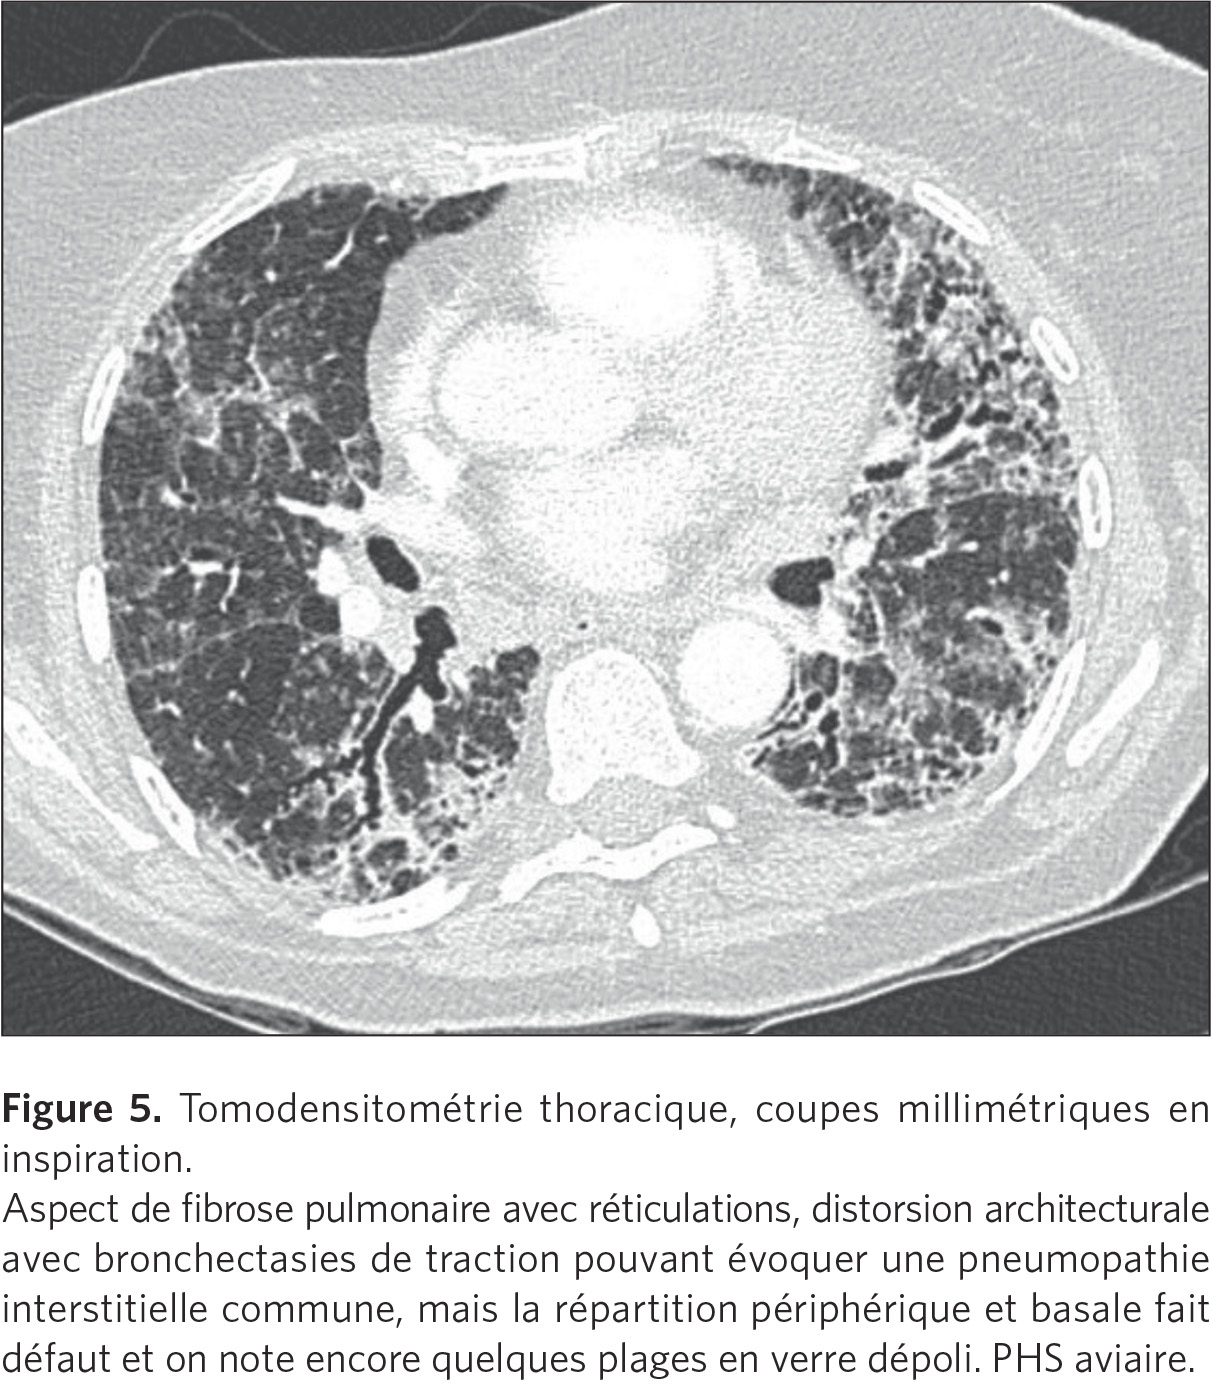

Mais on peut aussi voir des lésions de fibrose évoluées, où ce

sont les phénomènes de fibrose interstitielle qui se sont

développés, notamment dans les formes d’origine aviaire (figure

5).

Ces formes chroniques sont difficiles à reconnaître et peuvent

prendre le masque d’autres pathologies, comme la fibrose pulmonaire

idiopathique. Dans ces cas, il faut être très attentif aux signes

associés à la fibrose, qui peuvent être peu nombreux :quelques

granulomes, quelques images de trappage aérique, et à la

répartition des signes de fibrose qui sont plus situés dans les

champs supérieurs et moyens.